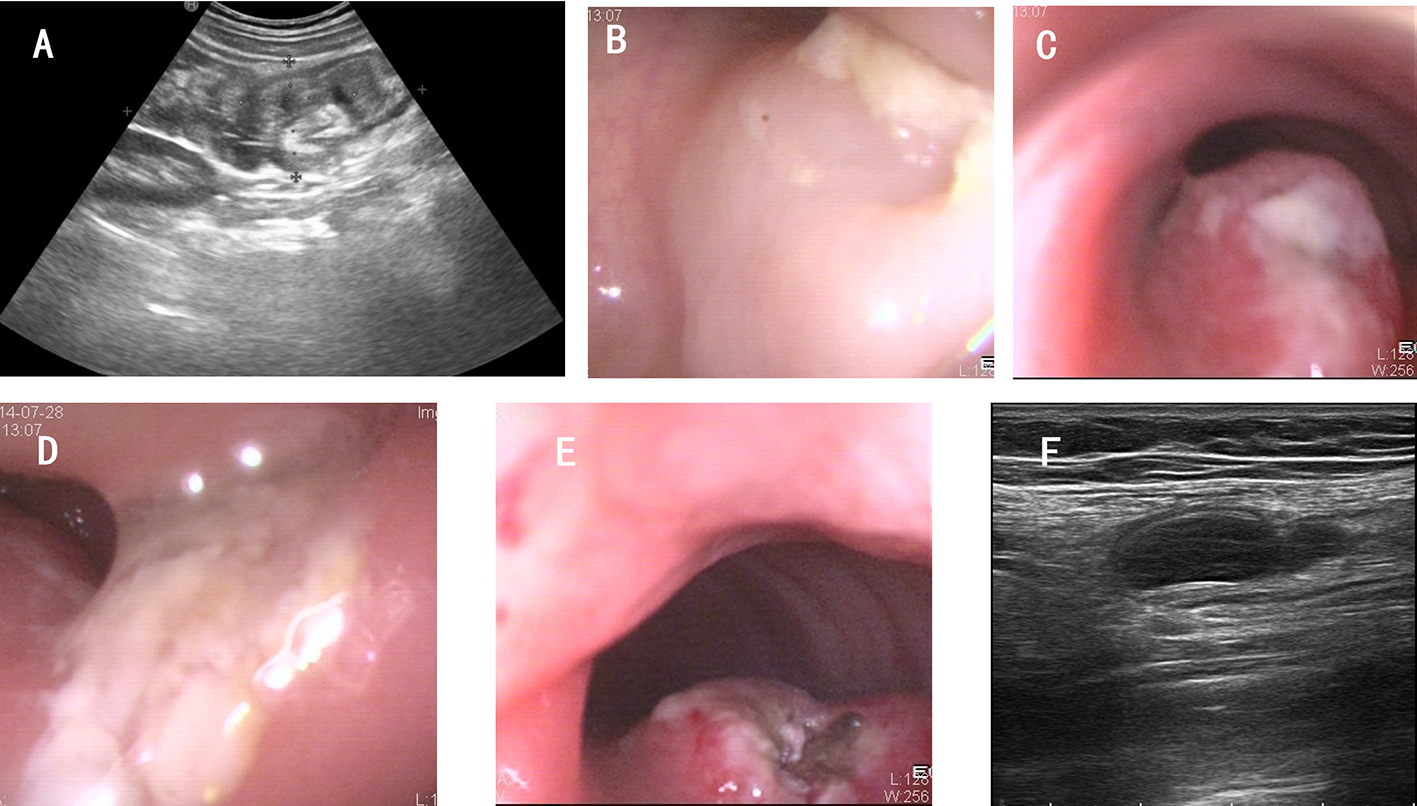

The intrahepatic bile duct is the relative blind area of SpyGlass. The treatment of intrahepatic bile ducts by retrograde transpancreatobiliary endoscopy can avoid the trauma of surgical choledochoscopy and sinus infection caused by percutaneous choledochoscopy. However, there are still few reports on the diagnosis and treatment of intrahepatic bile ducts by choledochoscopy in China and abroad, and they only concern grade-I and II intrahepatic bile ducts, even if currently the surgical choledochoscopic fiber can enter directly intrahepatic bile ducts above grade IV. In 2021, a study evaluated the effect of SpyGlass on grade-I and II intrahepatic bile duct lithotomy, whereas laser lithotripsis is performed for large or impacted gallstones at the same time. The results showed that the diagnostic rate of SpyGlass was 97.14%, the success rate of one-time lithotomy was 85.71%, the occurrence rate of complication was 8.57%, the postoperative residual stone rate was 14.28%, showing that SpyGlass can effectively diagnose and treat intrahepatic bile duct stones. But so far a multi-center study is still lacking to support its clinical promotion and application. In addition, SpyGlass can also be used to remove gallstones through the gallbladder duct while preserving it, with a high rate of stone removal, while being less traumatic, with rapid recovery and effective resumption of gallbladder function.